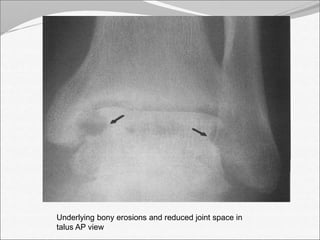

Underlying bony erosions and reduced joint space in

talus AP view

• 14.

Underlying bony erosionsand reduced joint space in talus AP view